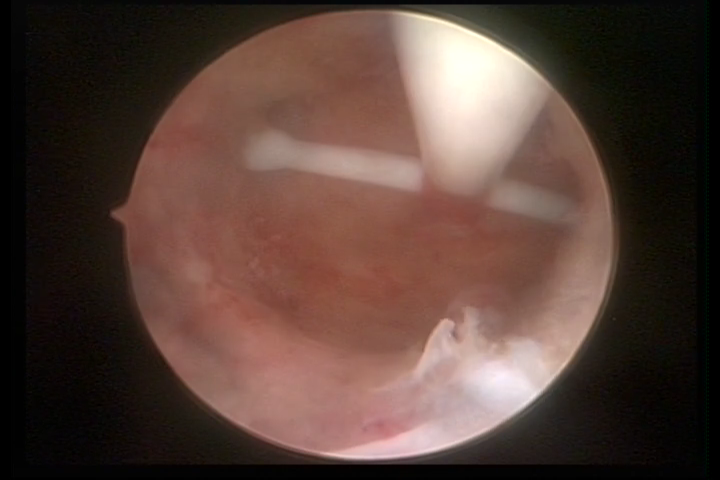

DIU normo inserido

×